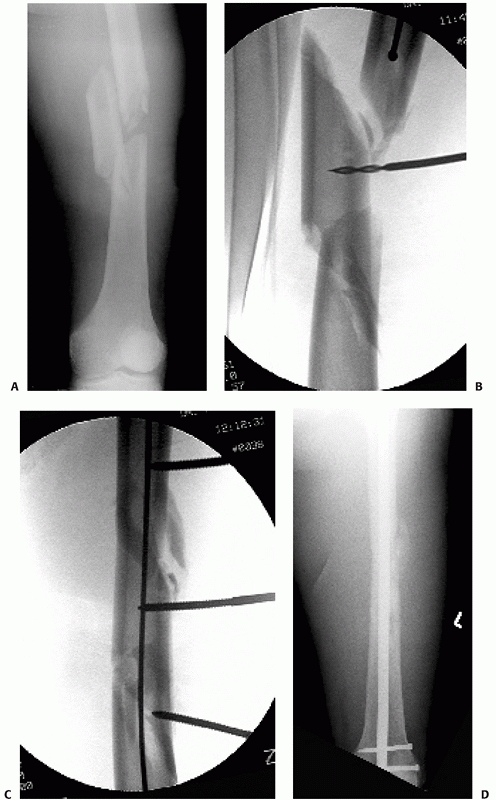

![]() |

FIGURE 50-9 A comminuted femoral diaphyseal fracture (A)

in a patient with multiple other injuries including a pulmonary contusion, liver laceration, and head injury. Temporary external fixation (B) was rapidly applied initially to provide stability and alignment. Conversion to an antegrade nail 7 days later resulted in uneventful healing (C). |